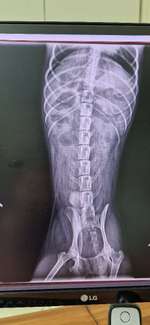

Also... mein Hund ist jetzt gute 3,5 und intakt. Mit gut 1,5 hatte er das Problem zum ersten Mal: leckte sich die Hoden wund. Tierärzt ...